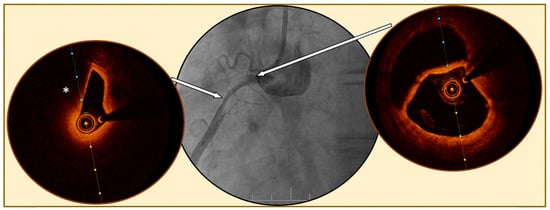

Figure 3.

Spontaneous coronary artery dissection evaluated by optical coherence tomography. Legend: Angiography of a right coronary artery (central figure) showing a diffuse tabular narrowing highly suspected for spontaneous coronary artery dissection. Optical coherence tomography (OCT) images confirm the diagnosis of a large dissection, with the presence of a false double lumen (right figure), at the beginning of the dissection (right arrow) and compression of the true lumen (left figure) by a diffuse circular hematoma (*) in the mid lesion (left arrow).